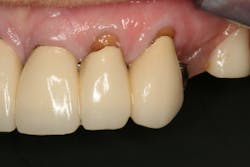

This clinical case began with a frustrated 75-year-old patient, who, after many years of failed attempts to repair the functional problem, came to the realization that a different solution was in order. The existing problem of an upper removable precision attachment partial denture was addressed first. The issue at hand was that the partial denture was perforated at the precision attachments, with the upper left side being more significant compared to the right side (figures 1–5). As a result, retention was adequate on the right side, but limited on the left. The patient was also concerned about esthetics, but needed a solution that kept a restricted budget in mind.

Dentition: Upper anterior splinted crowns had open margins and caries. Radiographs confirm decay, along with open margins (figures 6–11). Lower incisal anterior wear noted (figure 2).